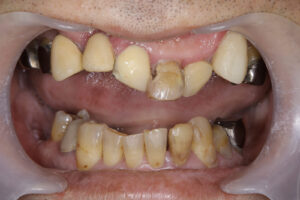

62歳男性

Underbite, crumbling teeth, orthodontics

咬合高径をあげれば受け口が改善される

ただし、奥歯には補綴が必要になる